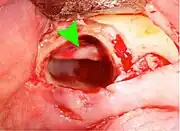

Wisdom teeth removal

Wisdom teeth removal (extraction) is the most common treatment for impacted wisdom teeth. In the US, 10 million wisdom teeth are removed annually.[21] The procedure can be either simple or surgical, depending on the depth of the impaction and angle of the tooth. Surgical removal is to create an incision in the mucosa of the mouth, remove bone of the mandible or maxilla adjacent the tooth, extract it or possibly section the tooth and extract it in pieces. This can be completed under local anaesthetic, sedation or general anaesthetic.[5] As of 2020, the evidence is insufficient to recommend one type of surgical practice over another.[22]